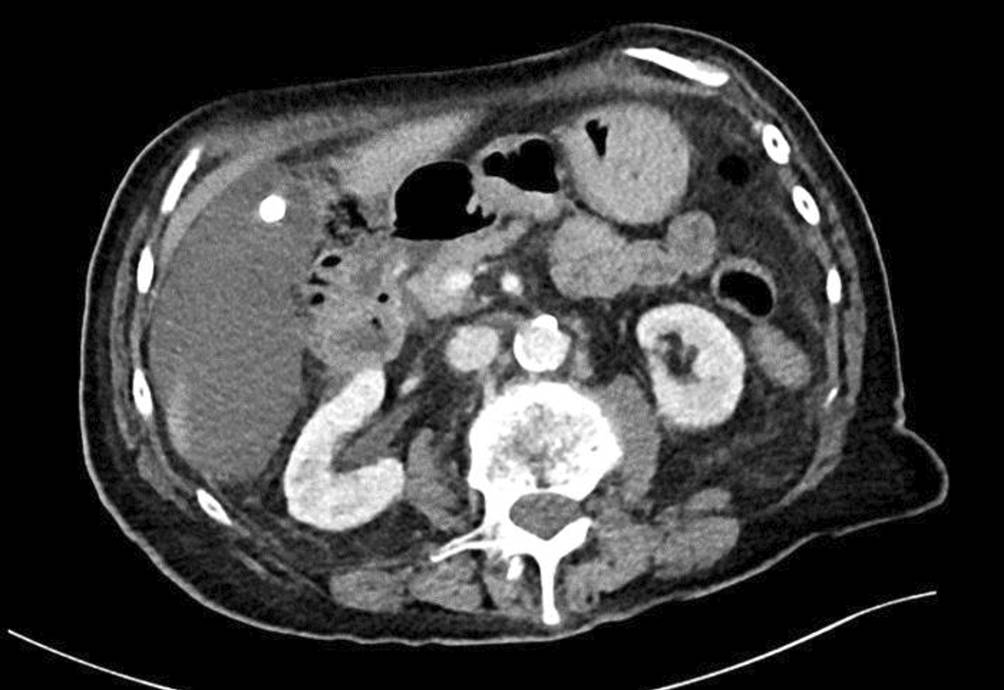

Die Vorstellung der 89-jährigen Patientin erfolgte über die Notaufnahme mit seit der Nacht bestehenden Oberbauchschmerzen und einmaligem Erbrechen. In der klinischen Untersuchung zeigte sich ein deutlicher Druckschmerz im rechten Ober- und Mittelbauch bei nur marginal erhöhten Entzündungswerten und normwertigen Cholestaseparametern. Sonographisch stellte sich ein Gallenblasenhydrops mit begleitender Entzündung und Cholezystolithiasis dar. In der unmittelbar ergänzten Computertomographie des Abdomens wurde der Verdacht auf eine akute Cholezystitis bei Cholezystolithiasis mit Hydrops und möglicher Perforation geäußert (Abb. 1).

Abb. 1

Computertomographie mit Darstellung der vergrößerten Gallenblase, Gallenblasenkonkrement und Umgebungsreaktion